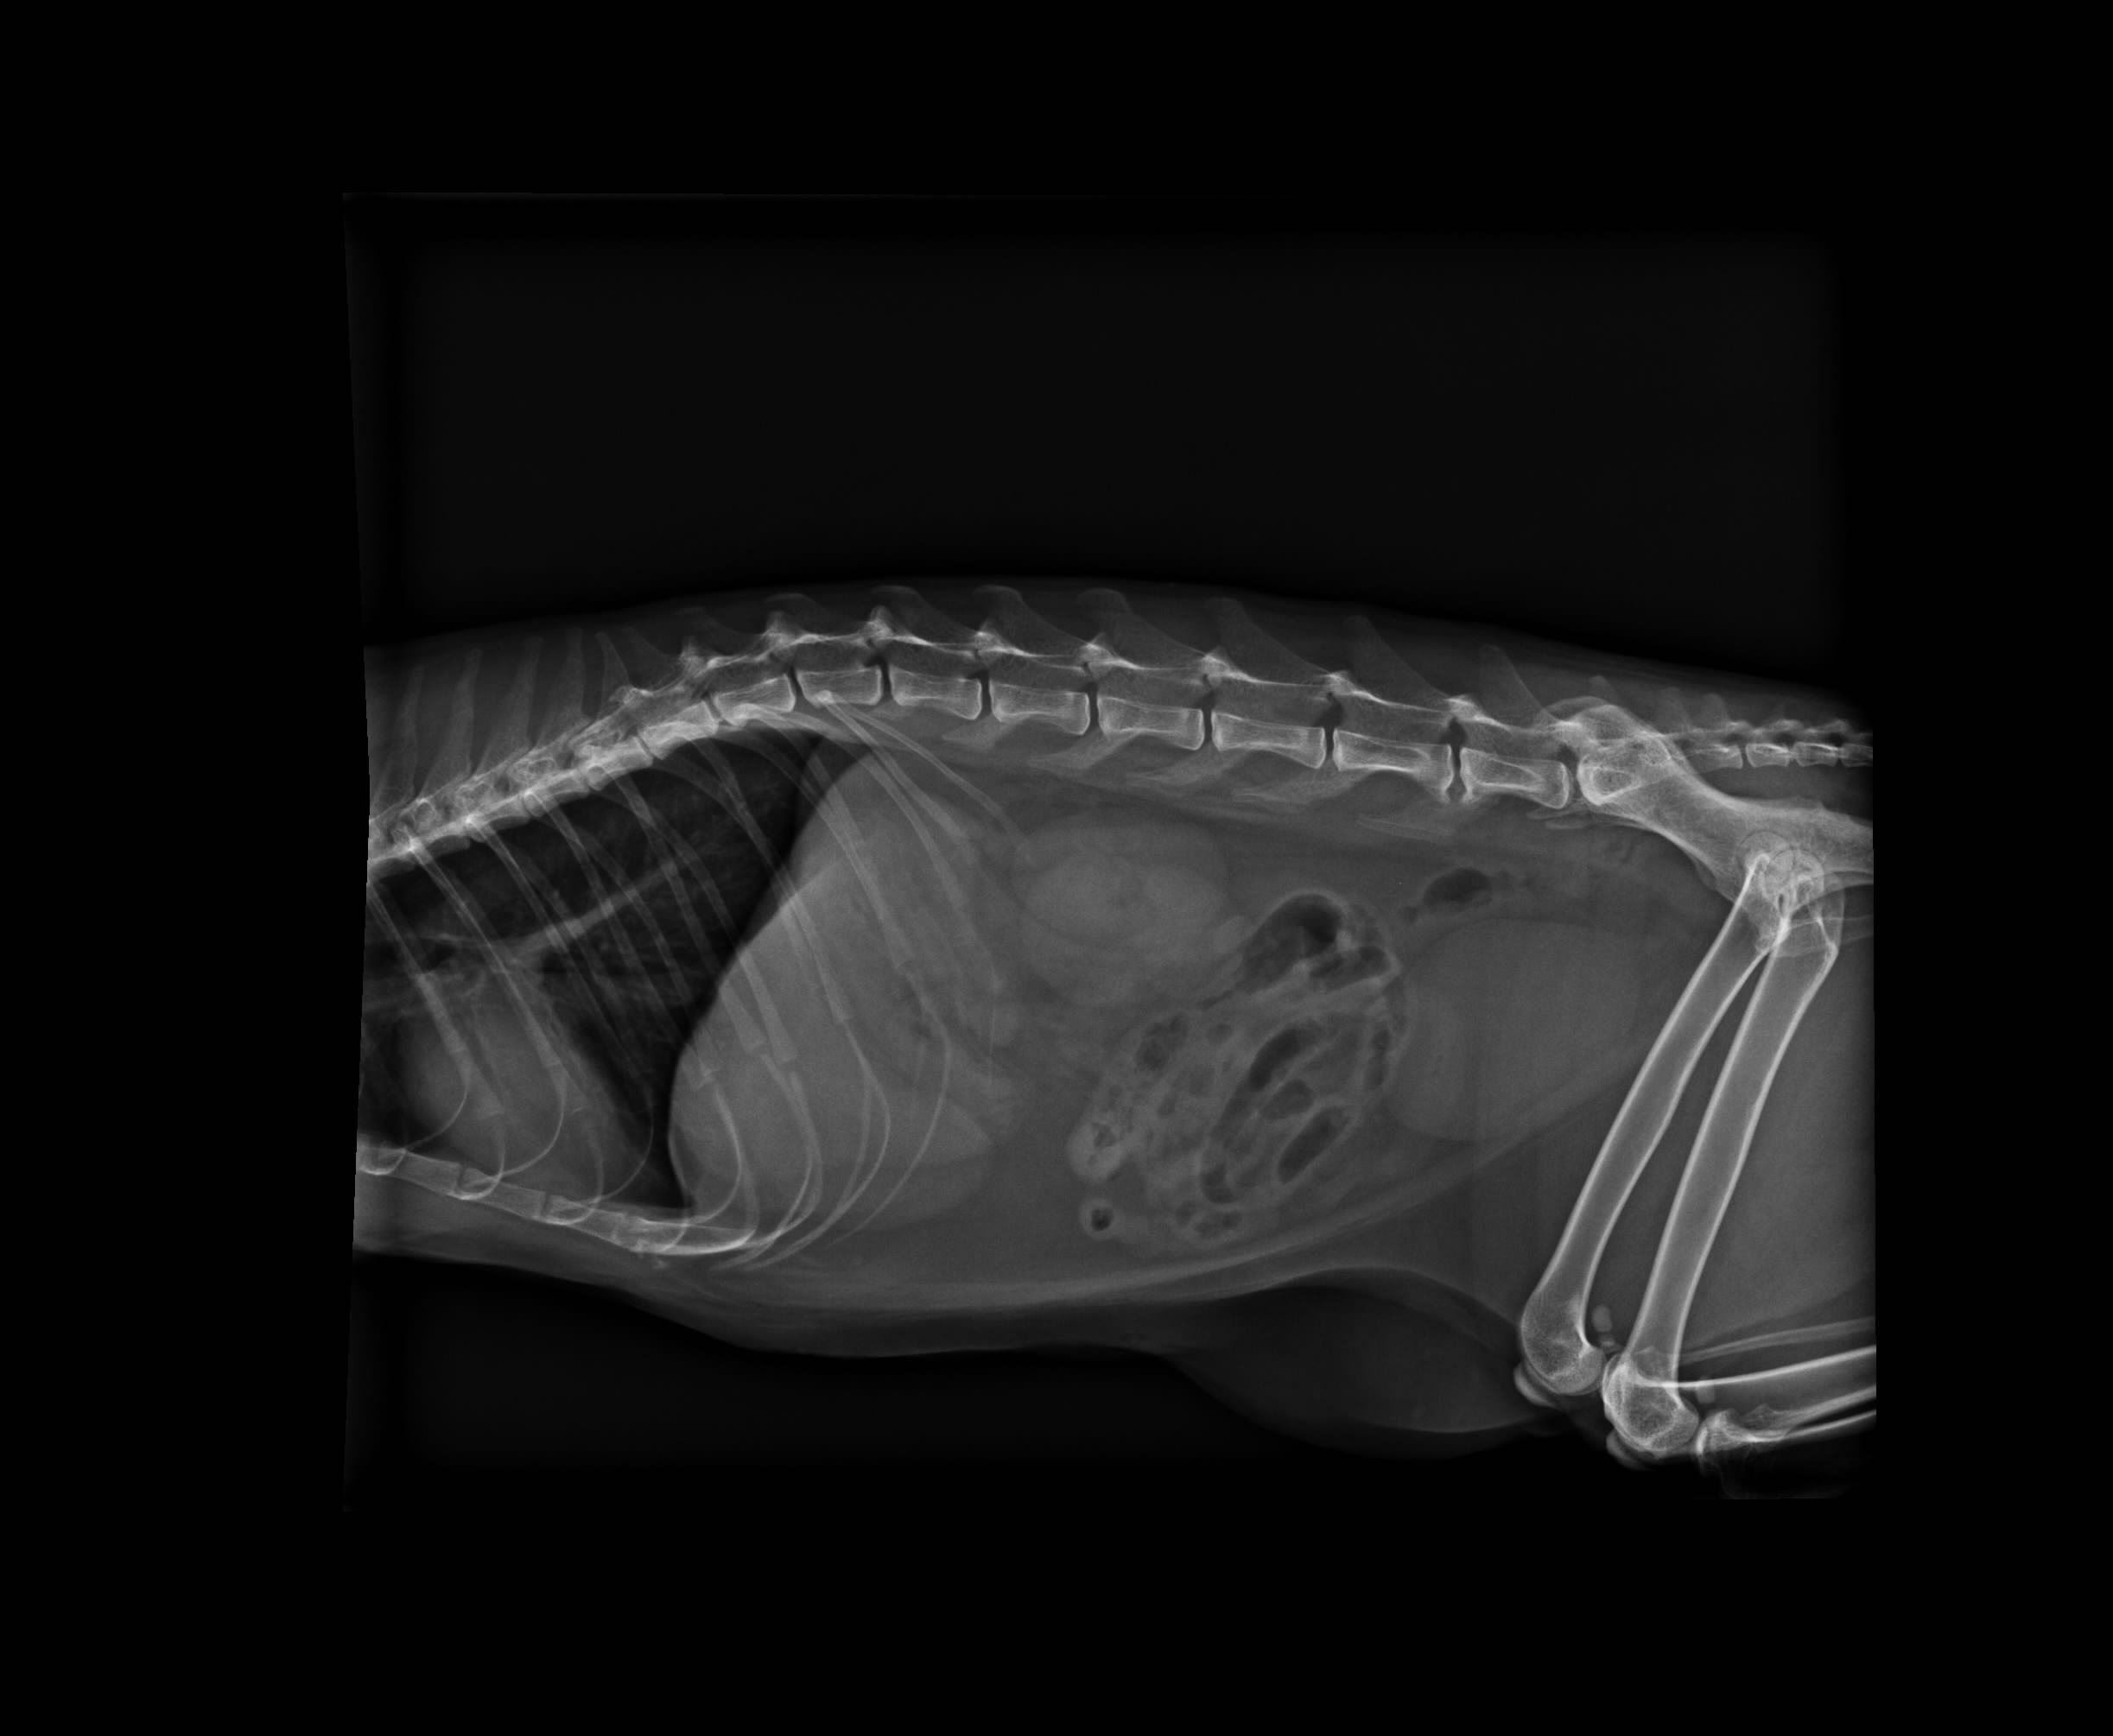

5.X-ray 400*2